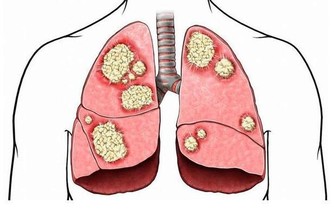

6.經常生病,缺乏蛋白質可導致免疫系統無法正常運轉。